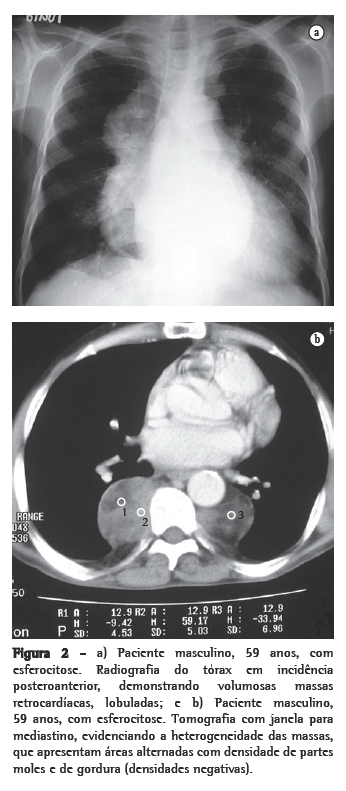

Dos seis pacientes, quatro apresentaram massas paravertebrais inferiores. Em três, elas eram bilaterais e relativamente simétricas, e em um era unilateral, à direita. Quanto ao conteúdo das massas, em três pacientes havia presença de tecido adiposo, sendo que em um desses o material gorduroso era bastante significativo. Em um paciente, as massas eram homogêneas, com densidade de partes moles (Figuras 1a e b, 2a e b).

Através da TC, podem ser observadas massas com densidade de partes moles, em sua maioria homogêneas, com características semelhantes às descritas na radiologia convencional,(1,2,5,6) que podem ou não ser realçadas após a administração do meio de contraste.(4,10) Este método de imagem é importante para analisar a estrutura interna das lesões, particularmente quando ricas em gordura,(5) para avaliar a presença de outras massas paracostais e para detectar alterações ósseas associadas a certas doenças hematológicas, como a talassemia e a anemia falciforme.(6) Nos casos relacionados a talassemia, anemia falciforme ou metaplasia mielóide, pode ocorrer um alargamento das cavidades medulares das costelas.(5)

As lesões ativas e recentes têm rica vascularização, enquanto que as antigas e inativas têm mais tecido gorduroso e deposição de ferro. Entre os dois extremos, existem várias combinações de achados, refletindo os diferentes estágios de evolução do foco hematopoiético. Os achados na TC e na RM de alguma forma traduzem essas diferenças histológicas. Lesões recentes e ativas têm densidade de partes moles na TC e intensidade de sinal intermediária na RM, tanto em T1 como em T2. Após a administração do meio de contraste, geralmente ocorre algum grau de impregnação nas lesões ativas. Lesões antigas e inativas podem mostrar aumento de densidade na TC, por impregnação pelo ferro, ou densidades negativas, pela infiltração gordurosa. Na RM, essas lesões podem mostrar alta intensidade de sinal tanto em T1 como em T2, pela infiltração gordurosa, ou baixa intensidade de sinal em ambas as ponderações, pela deposição de ferro.(4,8,12)